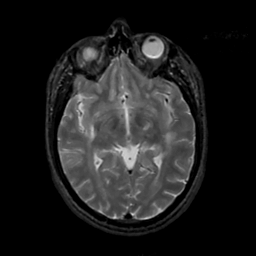

MR Study #3, February 24, 1991 -- Slice #23

[Home][Help][Clinical][Tour 1][Tour 2] Slice 23